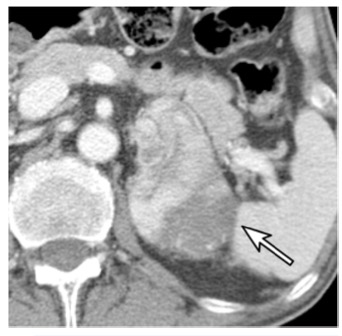

一名67歲的男性,患有乙狀結腸癌。增強CT圖像顯示左腎上腺有一個74毫米的結節(箭頭)。腎上腺切除術后,該結節被證實為腎上腺皮質癌。結腸癌經息肉切除術后確認為PT1期